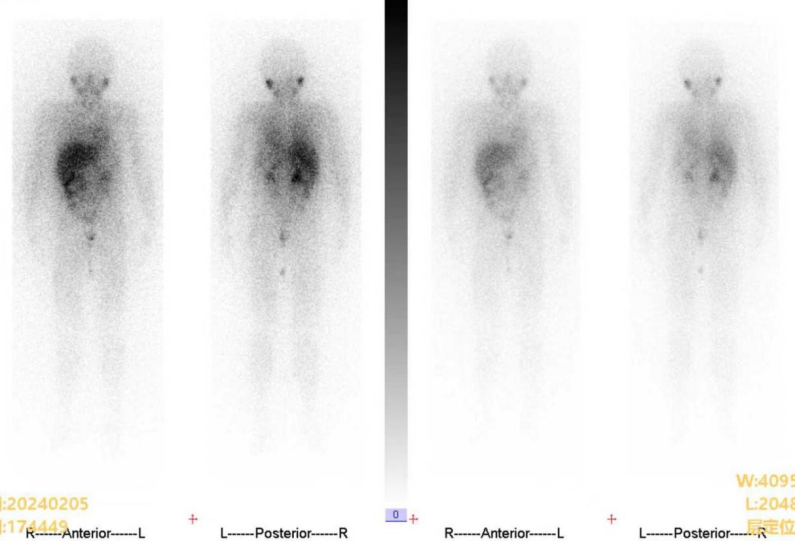

2024.02.05 MIBG检查:Curie评分0分。

2024.07.04 MIBG检查(末次MIBG复查):Curie评分0分。疗效评价:持续CR。